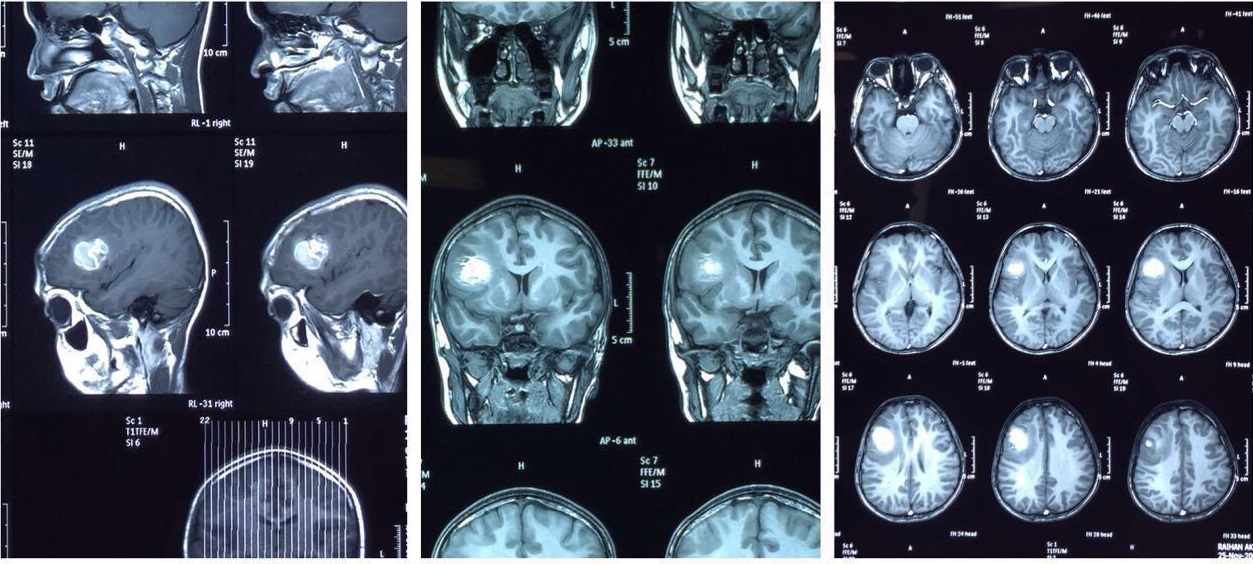

Hersenen: Een blik in de commandocentrale

MRI-scans zijn fantastisch voor het onderzoeken van de hersenen. Doktoren kunnen er allerlei dingen mee zien, zoals:

- Tumoren: Die vervelende "groeisels" kunnen soms verstopt zitten. De MRI kan ze vaak opsporen, zelfs als ze nog klein zijn.